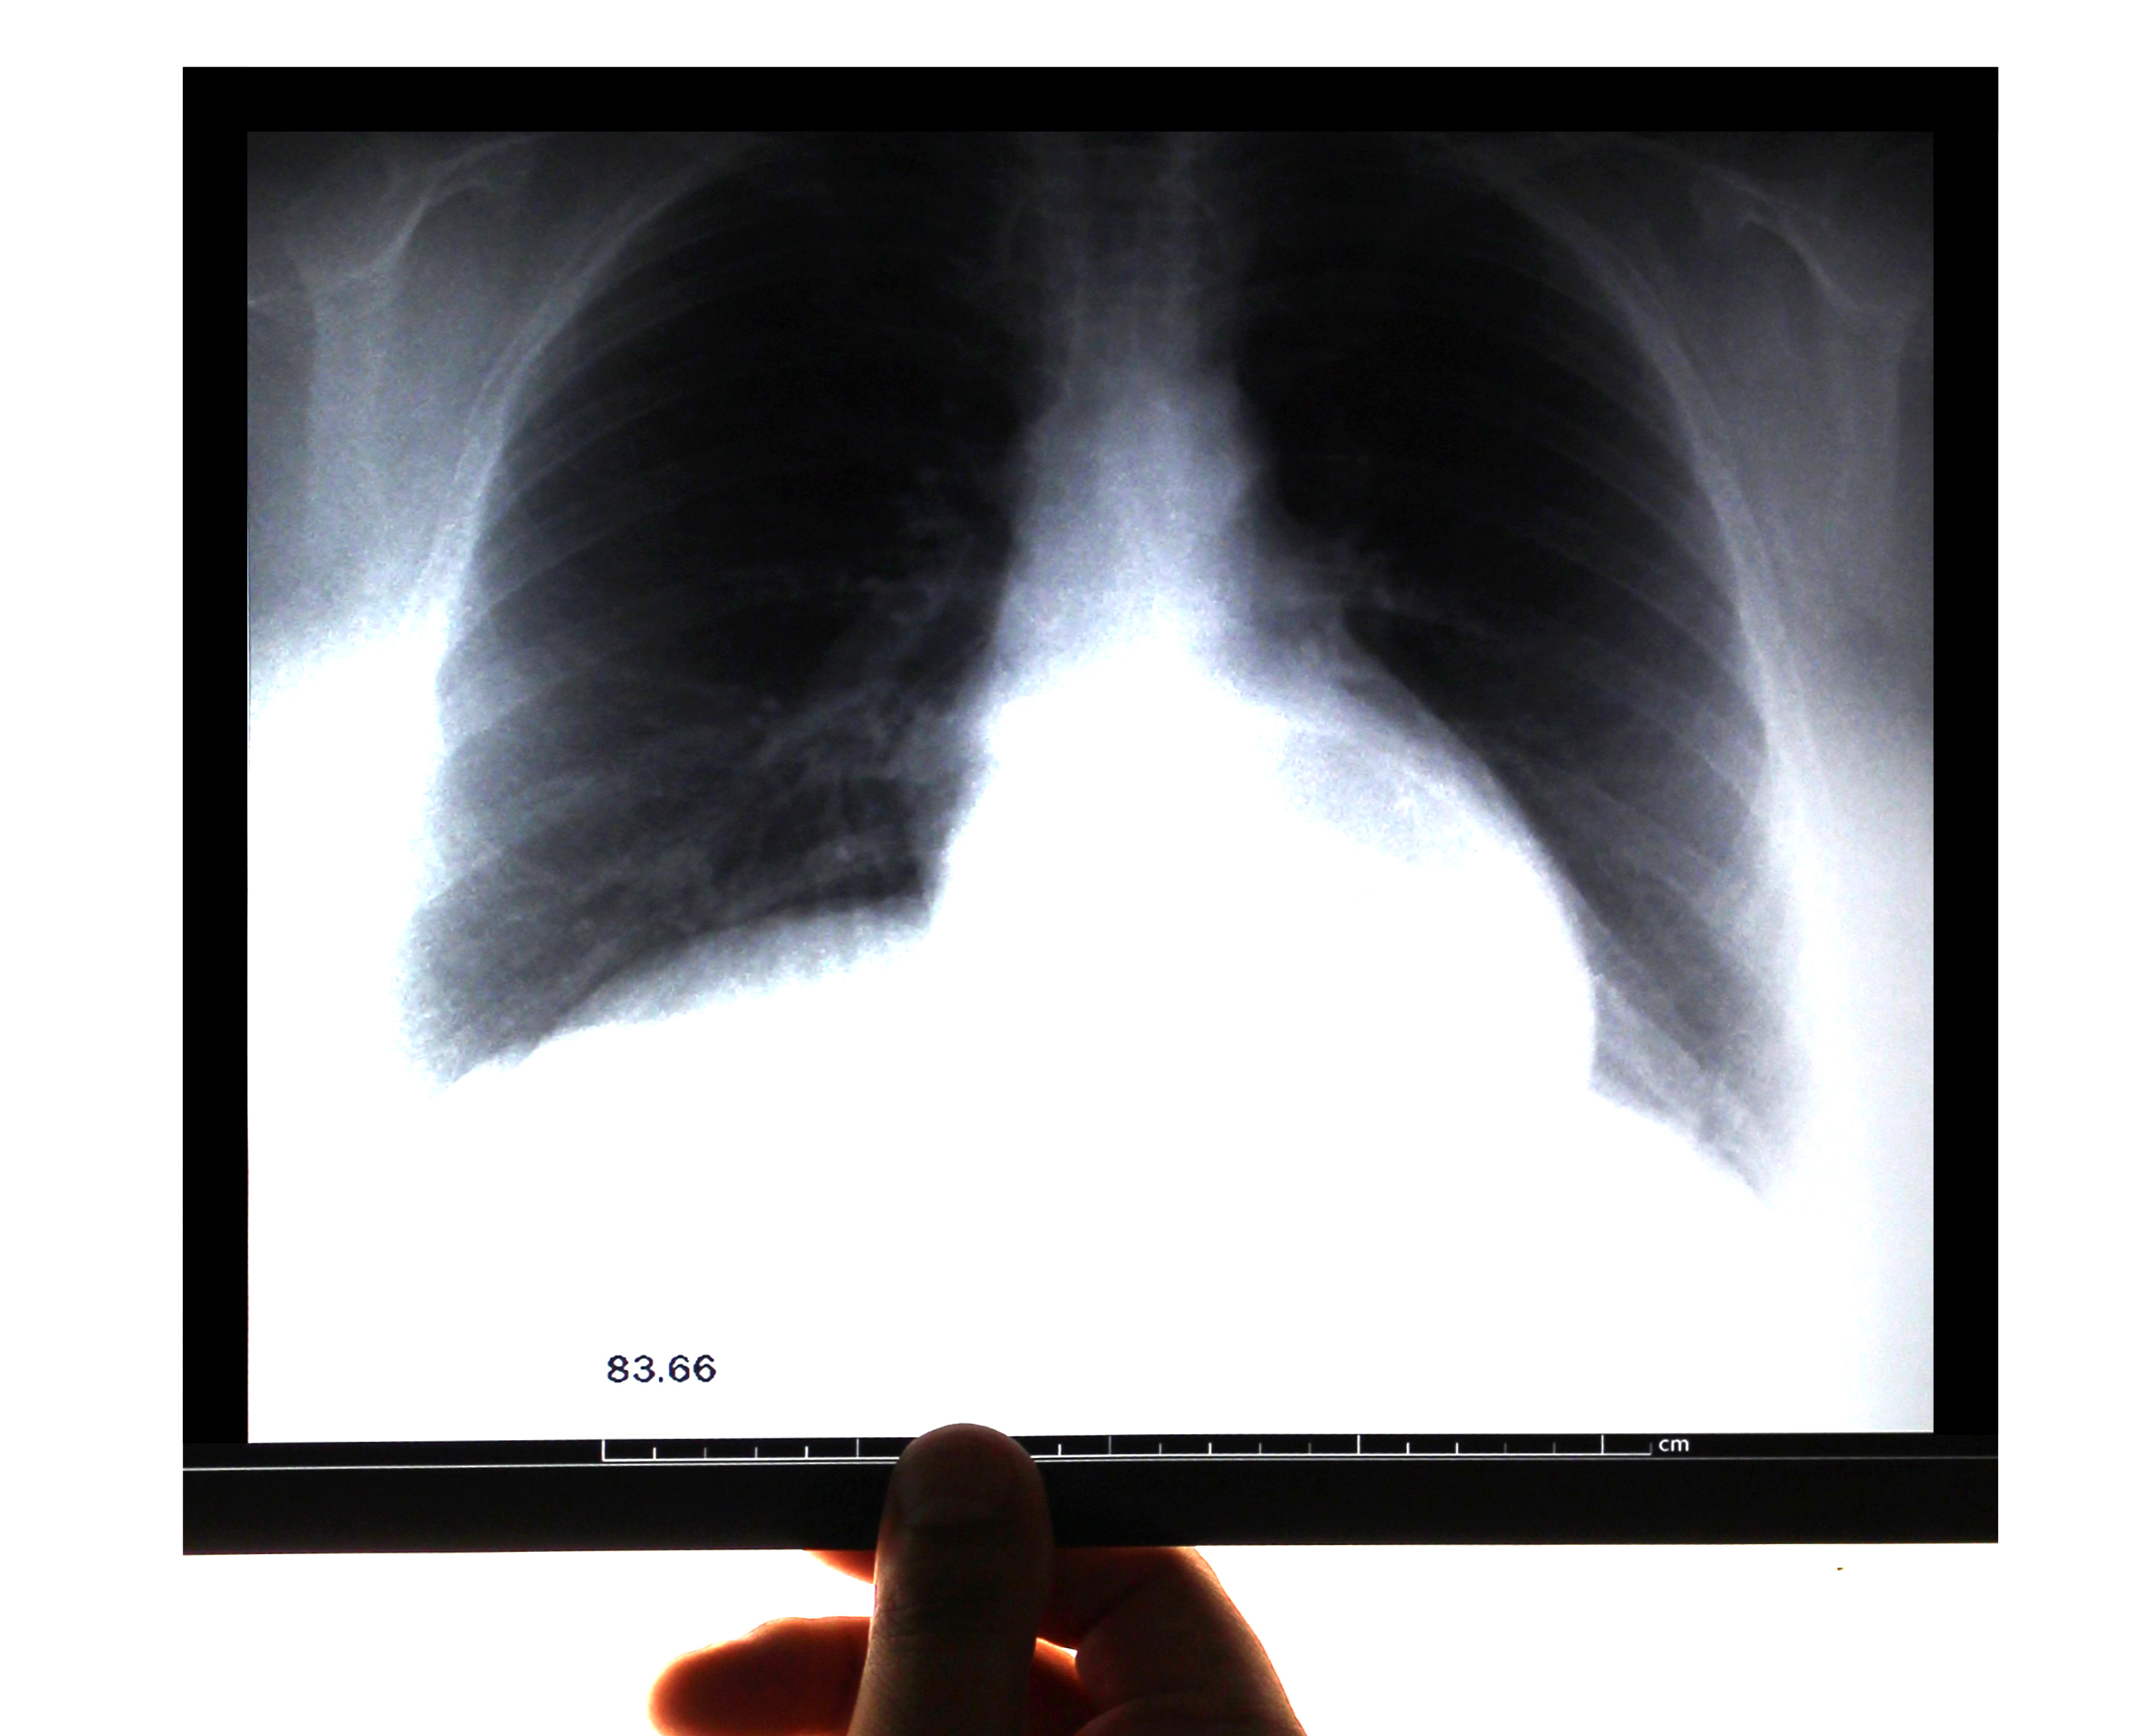

Бронхи человека исполняют важную функцию в процессах газообмена. Они очищают и согревают воздух, проводят его к легочной ткани, продуцируют слизь и защищают легкие от проникновения в них микроорганизмов. Очень часто подвергается воспалению именно бронхиальное дерево. Таким образом развивается обструктивный бронхит.

Обструктивный бронхит – это болезнь, которая характеризируется воспалением бронхов с их обструкцией. Данное заболевание осложняется отеком дыхательных путей и падением вентиляционной способности легочной ткани. Чаще всего обструктивный бронхит возникает у детей 3-10 лет, так как их дыхательная система не до конца сформировалась. Также бронхит может развиваться у взрослых и пожилых людей.

Течение острого обструктивного бронхита обычно не превышает 10-14 дней. Если человек кашляет более 2-3 недель, то можно говорить о переходе бронхита в хроническую стадию. Если симптомы возникают периодически, необходимо говорить о рецидивирующем хроническом бронхите. Диагноз хронический бронхит устанавливается, если кашель и отдышка мучают больного более 2 лет.